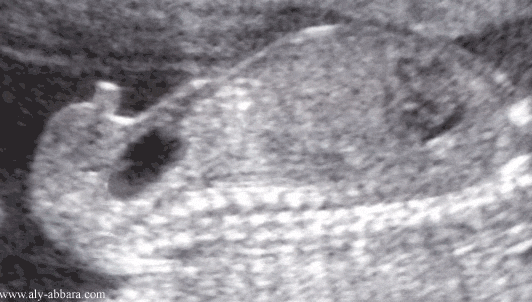

Coupe sagittale du tronc fœtal à 17 semaines d'aménorrhée

Fœtus du sexe masculin